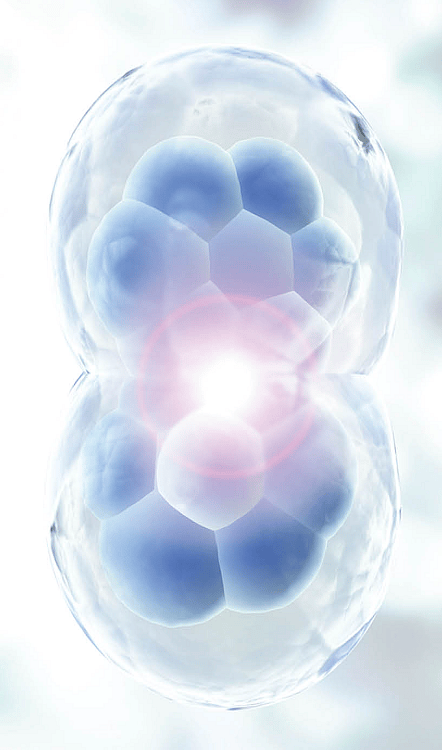

Çalışma, iltihabı azaltma ve hasarlı dokuları onarma ve yenileme yeteneği ile bilinen bir tür kök hücre olan Mezenkimal Kök Hücrelerin (MSC’ler) rejeneratif özelliklerini değerlendirdi. Vücutta doğal olarak bulunan MSC’ler, stres veya yaralanma alanlarını tespit ederek ve hasarlı hücreleri değiştirmek yerine vücuda kendi iyileşme sürecini başlatması için sinyal vererek biyolojik aracılar olarak işlev görür.

Bu klinik çalışmada, hastalar 18-30 yaşları arasındaki dikkatlice taranan sağlıklı donörlerden elde edilen MSC enjeksiyonlarını doğrudan etkilenen diz eklemlerine aldılar. Amaç, diz osteoartritinden muzdarip olanlar için cerrahiye potansiyel bir alternatif sunarak güvenliği doğrulamak, ağrıyı hafifletmek, iltihabı azaltmak ve kıkırdak hasarını potansiyel olarak onarmaktı.